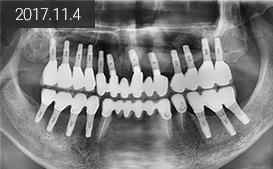

“ 지방에서 소개로 내원,

흔들리는 치아 발치 후

치조골 이식을 동반한 15개 임플란트 식립 후

19개 치아 복원 ”